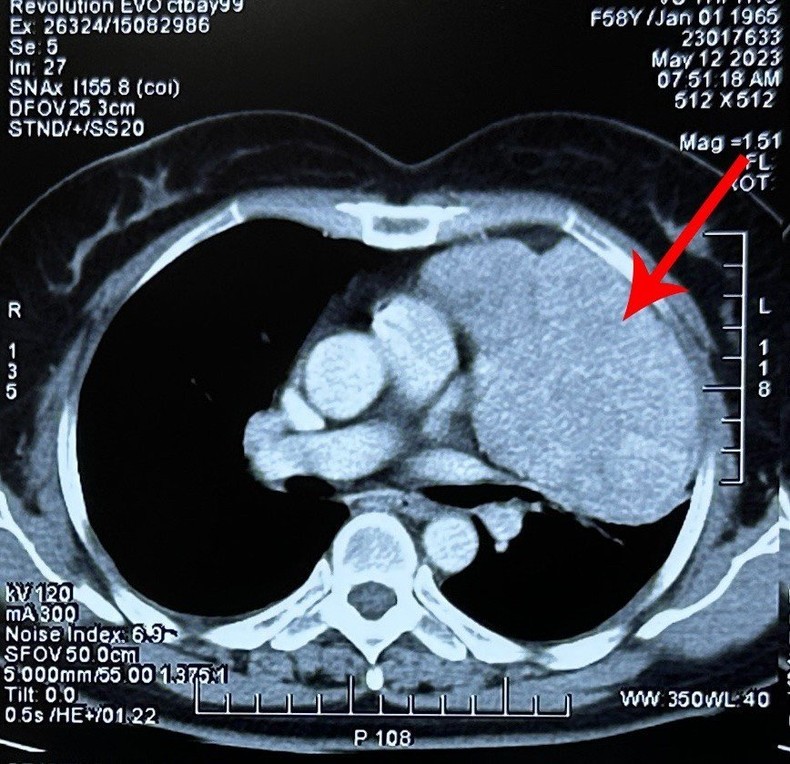

Trước đó, bệnh nhân sức khỏe hoàn toàn bình thường, không có dấu hiệu mệt mỏi, đau đớn hay khó chịu. Khi chuyển đến Bệnh viện Ung Bướu Hà Nội, qua các xét nghiệm chụp chiếu, các bác sĩ xác định khối u kích thước 11x10cm đã chèn ép gây xẹp gần như toàn bộ phổi trái, dính vào màng phổi, màng tim và dịch màng phổi tương đối dày.

Tiến sĩ, bác sĩ Phan Lê Thắng, Phụ trách Đơn nguyên Ngoại theo yêu cầu cho biết, khối u của bệnh nhân có kích thước lớn, nhiều mạch nuôi, gây tăng sinh mạch máu, dính các tạng xung quanh khiến quá trình phẫu thuật gặp nhiều khó khăn trong việc cầm máu và cắt u. Nếu không được phát hiện kịp thời, u phát triển xâm lấn cả hai phổi gây khó thở, suy hô hấp thì việc phẫu thuật sẽ càng khó khăn hơn.